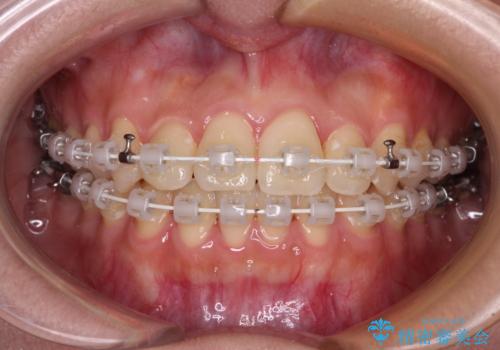

前歯のクロスバイトを短期間で解消 目立たないワイヤー矯正

- 審美装置

- 1年1ヶ月

- 前歯のクロスバイトを治したいとのことで来院された患者様です。

できる限り楽して、短期間で治したいとのことで、ワイヤー装置にて矯正治療を行うこととしました。